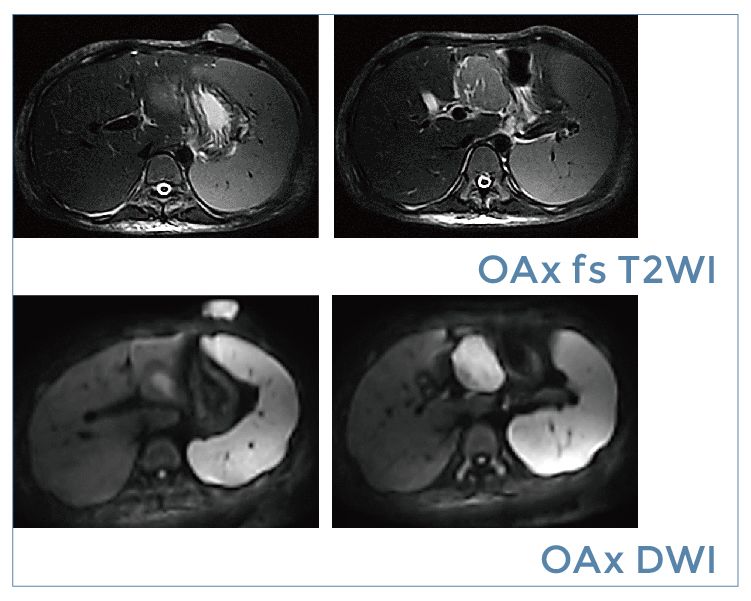

【朗润影像档案】磁共振影像病例分享(编号20190920)